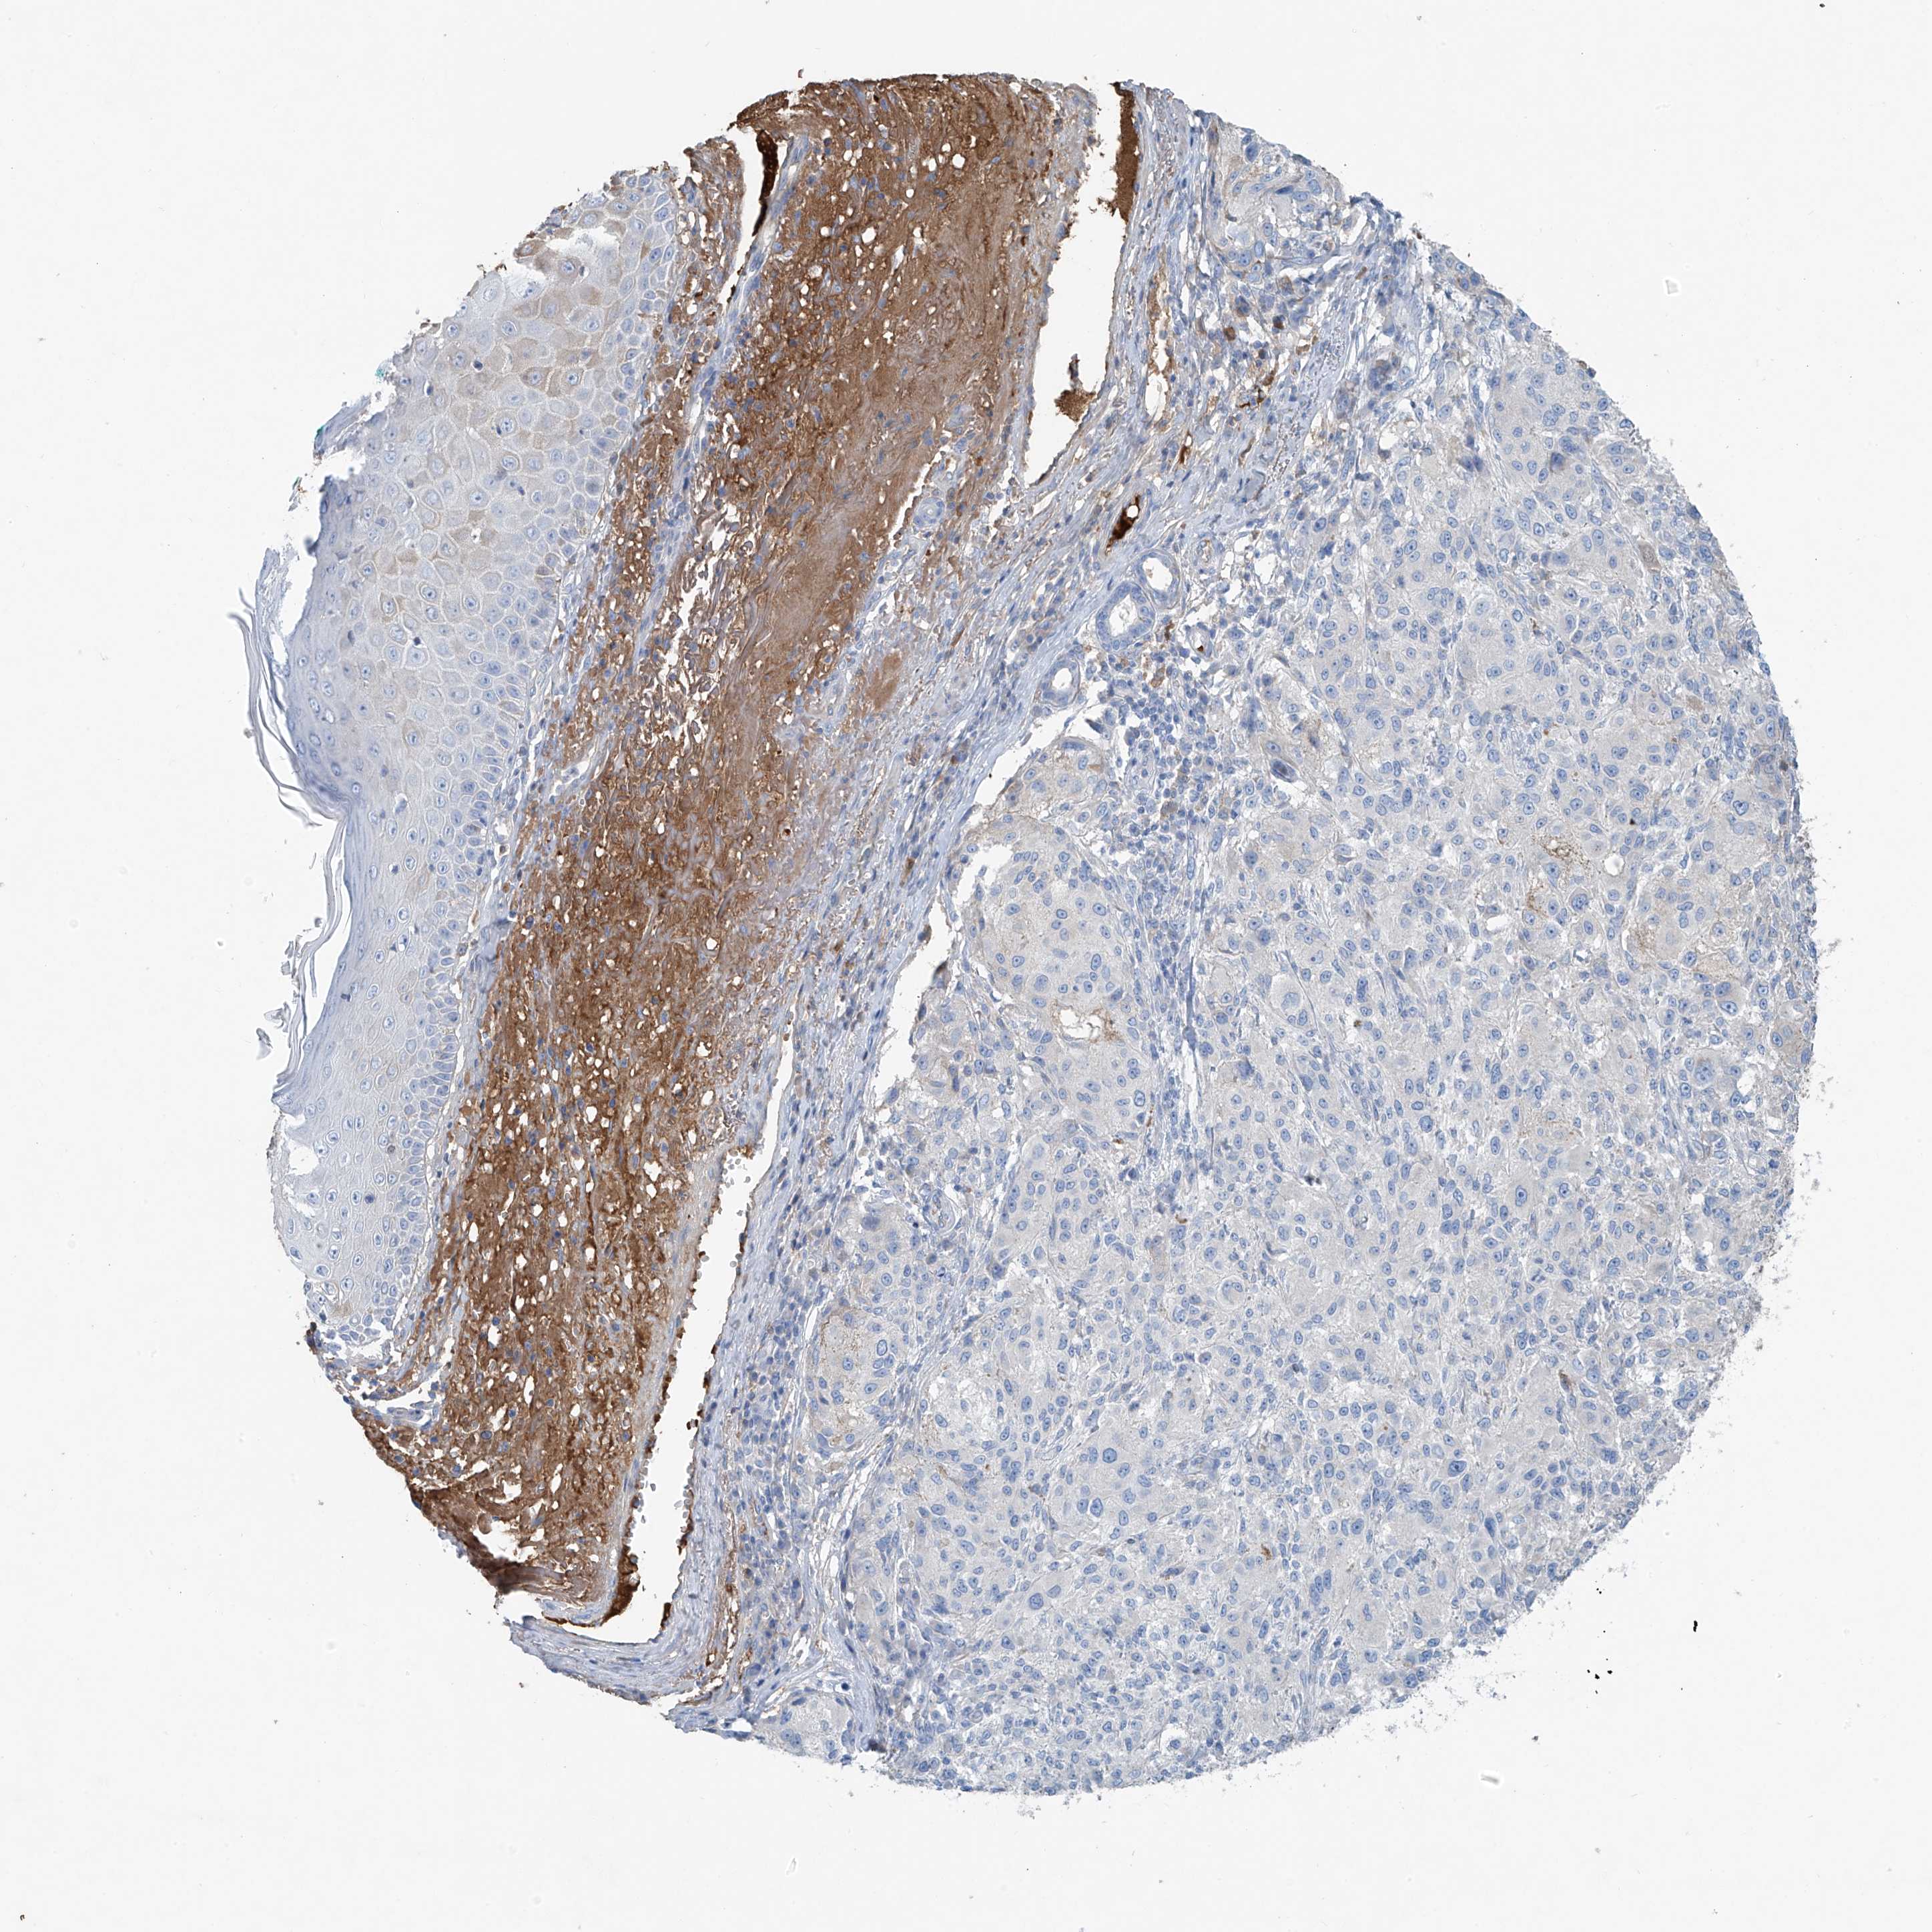

MELANOMA - Protein expressioni

A mouse-over function shows sample information and annotation data. Click on an image to view it in a full screen mode. Samples can be filtered based on level of antibody staining by selecting one or several of the following categories: high, medium, low and not detected. The assay and annotation is described here.

Note that samples used for immunohistochemistry by the Human Protein Atlas do not correspond to samples in the TCGA dataset.

Antibody stainingi

Antibody staining in the annotated cell types in the current human tissue is reported as not detected, low, medium, or high, based on conventional immunohistochemistry profiling in selected tissues. This score is based on the combination of the staining intensity and fraction of stained cells.

Each image is clickable and will lead to virtual microscopy that enables deeper exploration of all samples and also displays staining intensity scores, fraction scores and subcellular localization as well as patient and tissue information for each sample.

Antibody HPA009134

Staining

High

Medium

Low

Not detected

Intensity

Strong

Moderate

Weak

Negative

Quantity

>75%

75%-25%

<25%

None

Location

Nuclear

Cytoplasmic/membranous

Cytoplasmic/membranous,nuclear

Malignant melanoma, NOS

Malignant melanoma, Metastatic site